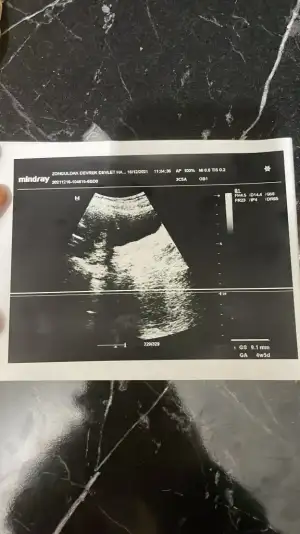

merhaba kızlar bende bir soru sormak istiyorum doktora gittim ultrasyon ile muayene etti iki ayrı ustrasyon kagıdı verdi birinde 4+5 9.1 mm birinde 4+6 9.8mm yazıyordu bu ne anlama geliyor kan degerinde 5355 cıkmıstı doktor bi acıklama yapmadı ikiz olma durumu varmıdır size nasıl kahıt vermişlerdi hatırlıyormusunuz

O Mm kesenin boyutudur. Henüz bebek bile oluşmamış olur bu haftada. 2 hafta sonra giderseniz daha net bilgiler elde edersiniz